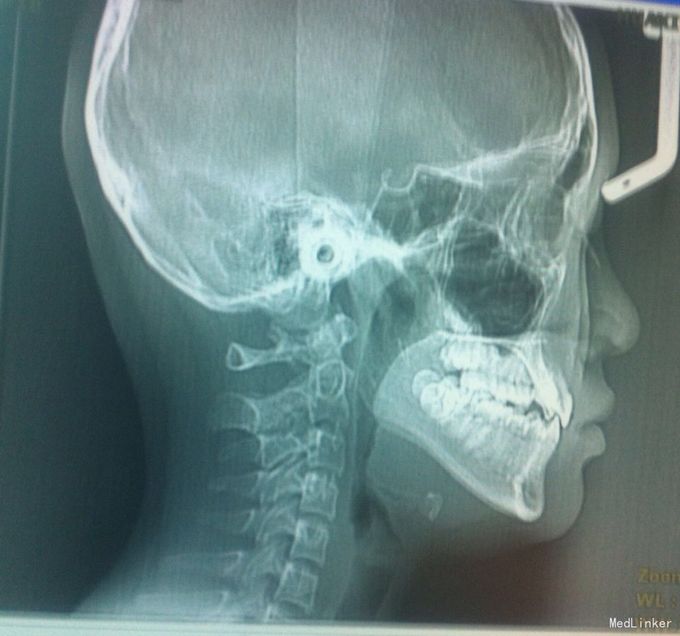

检查:恒牙期 右侧磨牙远中关系,左侧磨牙中性关系 前牙一度深覆合,正常覆盖 32、42未见 13、23唇侧错位 张口型异常 中线左偏约2mm 口腔卫生一般 X线未见32、42牙胚,28、38、48牙胚存在

诊断:安氏三类,先天缺牙 处理:拔牙矫治,直丝弓矫治器,拔除15、25,排齐整平上下牙列,关闭拔牙间隙,矫治后磨牙中性关系,前牙覆合覆盖正常,维持现有面型。

21牙X线示牙根较短,注意受力,防止松动脱落